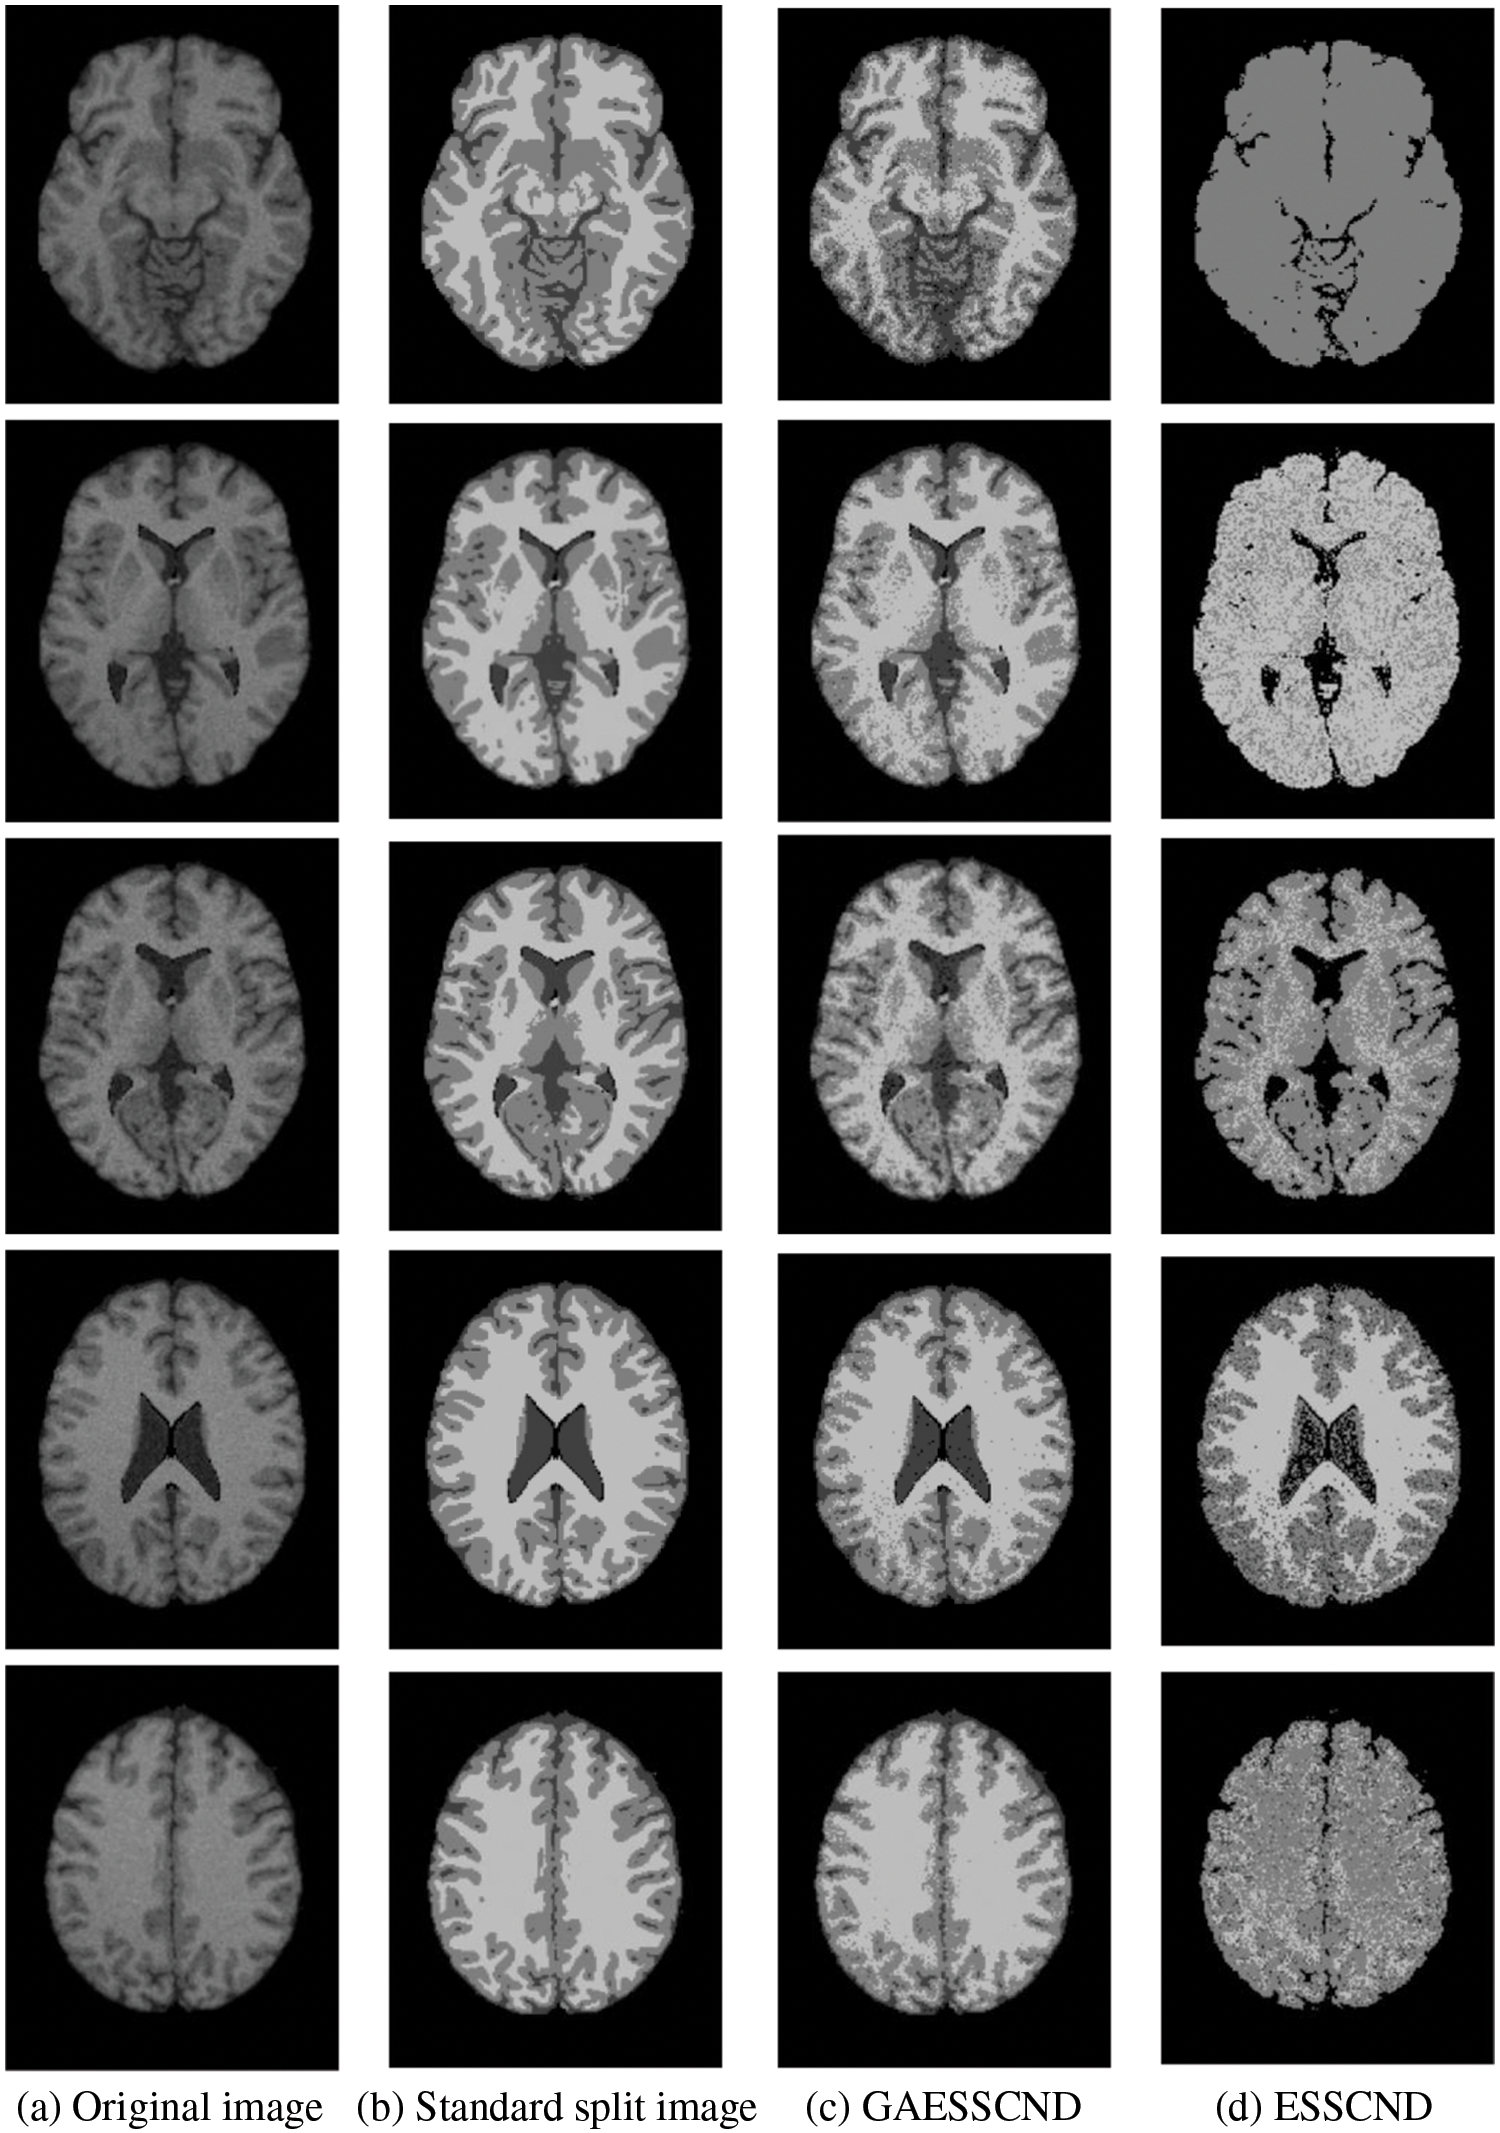

For the experiments in the previous subsection, experiments were conducted on publicly available medical brain MR images. In this chapter, the brain MR images provided by the imaging department of the First People’s Hospital of Changshu, Suzhou, China, were selected. In Fig. 4, (a) is the original image provided by the hospital, and the data were acquired by a Philips 3.0T standard MRI scanner with a 3D T1-weighted gradient echo sequence map. The parameters during scanning were as follows: TR = 5.5 ms, TE = 2.7 ms, layer spacing 0.3 mm, layer thickness 1.3 mm, FOV = 35 cm × 35 cm, image size 200 × 200 pixels, and each scan time was 60 s. In this paper, MR images of the clinical brain are used for experiments, and a variety of soft subspace clustering algorithms are used for comparison. The segmentation effect is shown in Fig. 4.

Figure 4: (a) shows the real brain MR image provided by the hospital, (b) shows the segmentation effect of the proposed algorithm, (c) shows the segmentation effect of the ESSCND algorithm, (d) shows the segmentation effect of the ESSC algorithm, (e) shows the segmentation effect of the KESSC algorithm, (f) shows the segmentation effect of the FSC algorithm, and (g) shows the segmentation effect of the EWKM algorithm

The second row in Fig. 4 is the real MR image provided by the hospital, and the image contains 5 classes: 0 = Background, 1 = CSF (cerebrospinal fluid), 2 = Gray Matter, 3 = White Matter, and 4 = Skull; these 5 classes are segmented by clustering segmentation. Table 2 shows that the GAESSCND algorithm is able to segment the 5 classes with clear boundaries, while the rest of the comparison algorithms have poor results in the face of noise processing, with mixed boundaries and mis-segmented brain tissue.

Due to the lack of truth maps in the dataset provided by the hospital, the evaluation metrics were chosen from the internal evaluation metrics in MATLAB. Davies–Bouldin index (DBI) [48] silhouette coefficient (SC) [49].

In Table 3, it can be seen that the proposed GAESSCND algorithm segmentation yields the best results with the smallest DBI coefficient, the strongest similarity in each cluster class, and the largest contour coefficient SC, segmenting significantly and outperforming other clustering algorithms. In the experimental process of Fig. 3, the KESSC algorithm has most of the kernel space with zero, resulting in obvious deviation of the weight contribution; the experimental segmentation effect is poor, and the corresponding evaluation index result is NaN.

Because in the MR imaging process, the real and imaginary parts of the signal are disturbed by Gaussian noise with uncorrelated zero mean and the same variance at the same time due to the influence of environment and equipment, in order to verify the anti-noise property of GAESSCND, the noise addition process is performed again for the image to simulate the problems of blurred boundary and poor visual effect after the MR image is subjected to noise by adding speckle noise to the image provided by the hospital, taking the value of 0.03. By comparing the experiment with other soft subspace clustering, the segmentation effect obtained is shown in Fig. 5.

Through the experiments, (a) in Fig. 3 is the image after noise, and the (b–g) columns are all the effects after clustering segmentation of the brain MR containing noise. From a visual perspective, the GAESSCND algorithm has the strong anti-noise ability, among which KESSC has segmentation failure for serial numbers 3 and 4 and cannot segment the brain tissues in the images containing noise. Under the influence of noise, KESSC affects the weight allocation in nuclear space, most of which has zero weight. After the cluster center and membership fall into the local optimal solution in the iteration, the experimental results are wrong, and the brain tissue cannot be segmented from the image containing noise. KESSC is also more suitable for high-dimensional datasets and does not have a good processing advantage for noisy data. From the experimental data obtained in Table 4, it can be seen that GSESSCND shows very good results for all five noise-added brain MR images. The rest of the soft subspace clustering shows insufficient noise immunity for the images with noise, and the brain MR images are segmented incorrectly.

Finally, the GAESSCND algorithm showed good clustering results for both hospital-supplied MR images and noise-added images, reflecting the robustness and noise resistance of the algorithm. From some of the compared soft subspace clustering algorithms, the rest of the soft subspace clustering showed unclear boundary segmentation, high noise content, and unclear soft tissue segmentation.